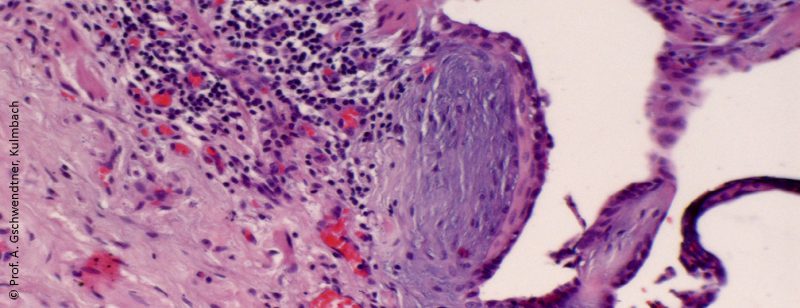

Invasive Diagnostik diffuser parenchymatöser Lungenerkrankungen

Für die Differenzialdiagnose der idiopathischen Lungenfibrose (IPF) als einer der häufigsten Formen der idiopathischen interstitiellen Pneumonitiden ist in manchen Fällen eine histologische Diagnose notwendig. Für den Fall, dass eine invasive...…